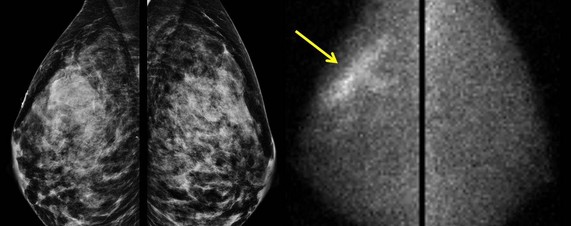

Рак молочной железы фото

Огромную роль в предупреждении любых заболеваний молочной железы является диагностика и своевременное выявление любых патологий на ранних стадиях. Все симптомы, по которым определяются любые изменения в области груди указаны выше. Современная дерматология и онкология используют проверенные годами методы: внимательный внешний осмотр больного, пальпацию, маммографию, УЗИ и проведение цитологических исследований на основе пункций, взятых из подозрительных новообразований.

Как выглядит начальная стадия рака молочной железы?

На начальном этапе злокачественного процесса в ткани молочной железы обнаруживается незначительного размера, не более 2 сантиметров, новообразование. При этом окружающие ткани не затронуты, в регионарных лимфатических узлах и отдаленных органах не выявляются метастазы.